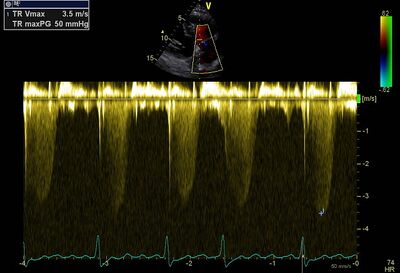

| TR Vmax

<2.8 m/s

2.9-3.4 m/s

>3.4 m/s

Calculations for estimating pressure in the pulmonary artery

| Systolic PA pressure

4 x(TR Vmax)2 + estimated RA pressure

Examples of severe pulmonary hypertension1

| Increased Systolic PA pressure